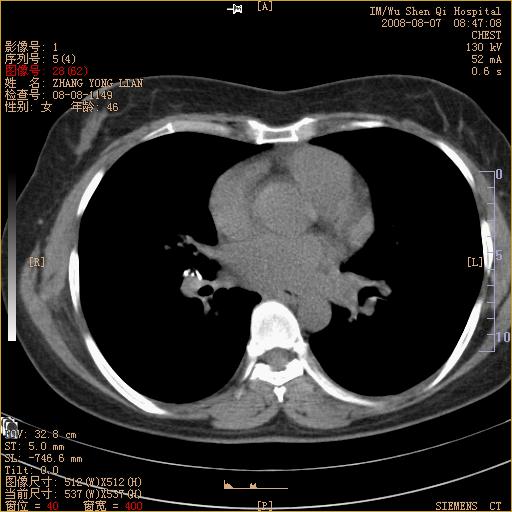

标题: CT15050:女,46岁,咳嗽胸痛一月余 [打印本页]

纵隔窗没发全,左下肺近胸膜处结节。有长毛刺,纵隔淋巴结增大,不排除恶性病变。

考虑肺癌

考虑左肺下叶后基底段周围型肺癌伴纵隔淋巴结转移可能性大。

左下肺ca并纵隔及左肺门区淋巴结转移。

1)考虑左肺下叶后基底段周围型肺癌伴纵隔淋巴结转移。2)脾内低密度灶,性质待定;不排除转移瘤可能。